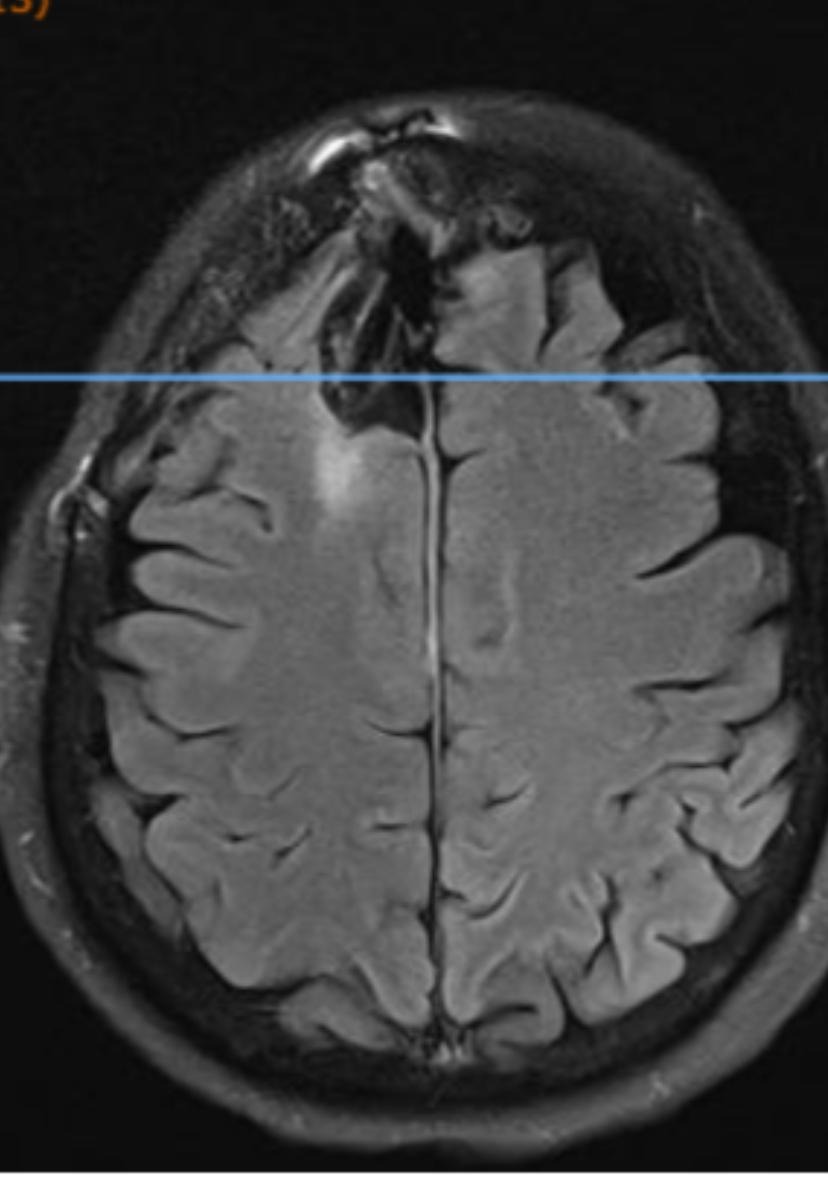

After undergoing an MRV of my brain on 08/14/2025, my neurooncologist called me on Monday, 08/18/2025 and informed me that I have another small brain tumor that is pressing up against the superior sagittal sinus vein in my brain, a large vein that drains blood and cerebrospinal fluid and helps to prevent hemorrhage and stroke, and that I must watch my stress since the MRV showed the tumor is severely constricting the vein.. as I could easily have a stroke or hemorrhage. Unfortunately she told me that the tumor is not operable as it is too risky to remove a tumor that is attached to such a large vein as it would likely cause a fatal brain hemorrhage during surgery. She is particularly concerned about the tumor growing and causing serious life-threatening issues because the large tumor I had removed was very aggressive and atypical, grade 2-3. She additionally informed me that I have yet another brain tumor discovered in the posterior (back) part of my brain that is also inoperable if it grows and starts to cause me further problems. I will continue having brain MRIs every 6 months to check for tumor growth.

My name is Christine. Please bear with me as I try to give an abbreviated version of a long story. I underwent two urgent brain surgeries, six days apart, approximately five months ago, to remove a massive 8.5 cm cancerous brain tumor. I spent two weeks in the ICU and 31 days in the hospital in Roanoke, VA. After the first brain surgery, I was told I had a blood clot on the top of my brain, for which I am continuing daily medication. It is called a CVST, which is a rare stroke. .. five days after my first surgery I was told I would need a second brain surgery because there was still some of the tumor left that needed to be removed.